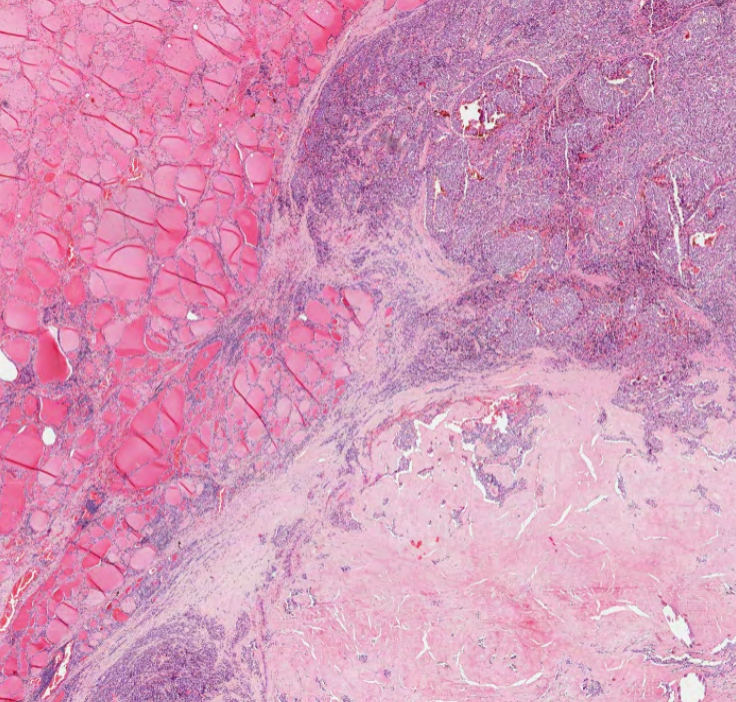

Since 2003, we have been creating one of the largest pathology educational resources online.. completely open access and free to use for non-commercial activities.. please get in touch for educational collaboration or commercial use 👍 any use pls credit: virtualpathology.leeds.ac.uk